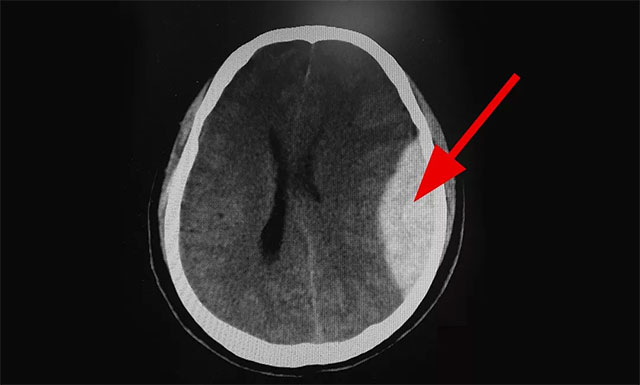

近日,上海藍(lán)十字腦科醫(yī)院急診科就收治一名酒后的男性患者,其意識(shí)不清,并不慎摔倒,而自己卻不知道,造成左側(cè)額頂葉急性硬腦膜外血腫伴腦疝形成,情況危急,幸好搶救及時(shí),已脫離了生命危險(xiǎn),之后也未留下任何后遺癥。

▲ 患者出血嚴(yán)重,情況危急

10:01,CT檢查結(jié)果顯示:患者為左側(cè)額頂葉急性硬腦膜外血腫伴腦疝形成,病情非常危急,卒中小組立即聯(lián)系腦血管病區(qū)主任張琪博士,隨后完善各項(xiàng)檢查,待手術(shù)準(zhǔn)備就緒,行左側(cè)額頂葉急性硬腦膜外血腫清除術(shù)。